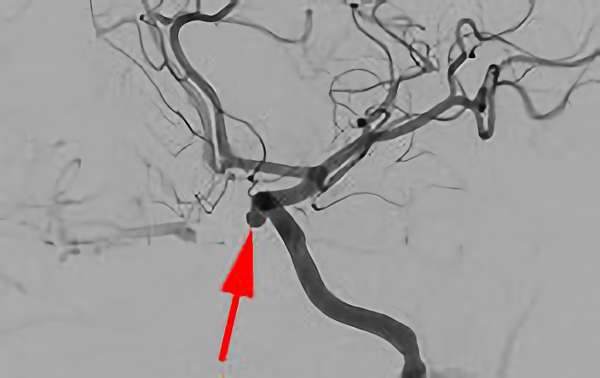

No.1630 手術前